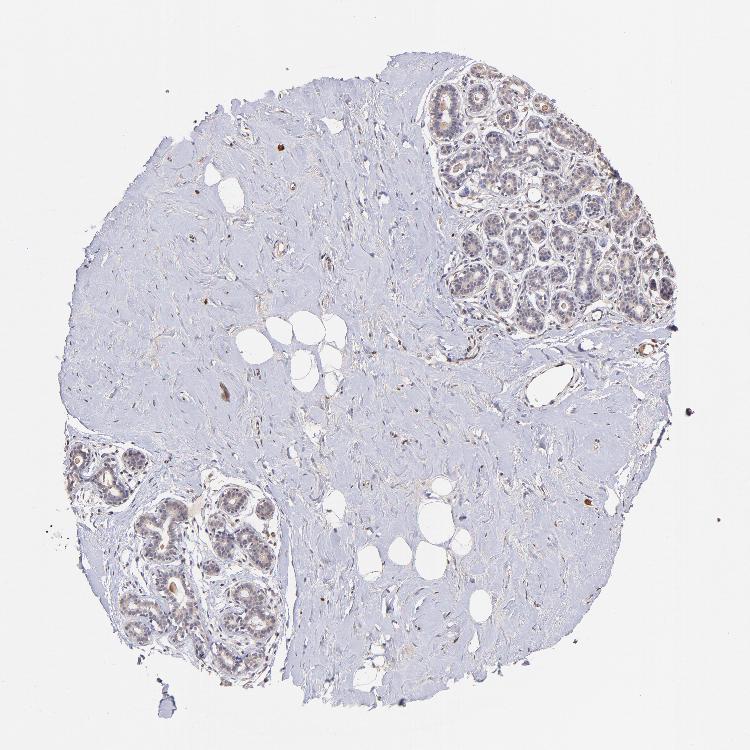

BREAST - Antibody stainingi

Antibody staining in the annotated cell types in the current human tissue is reported as not detected, low, medium, or high, based on conventional immunohistochemistry profiling in selected tissues. This score is based on the combination of the staining intensity and fraction of stained cells.

Each image is clickable and will lead to virtual microscopy that enables deeper exploration of all samples and also displays staining intensity scores, fraction scores and subcellular localization as well as patient and tissue information for each sample.

Antibody HPA002633Antibody HPA046758Antibody CAB010906

Adipocytes Not detected-Not detected

Glandular cells Not detectedHighMedium

Myoepithelial cells Not detectedHighMedium